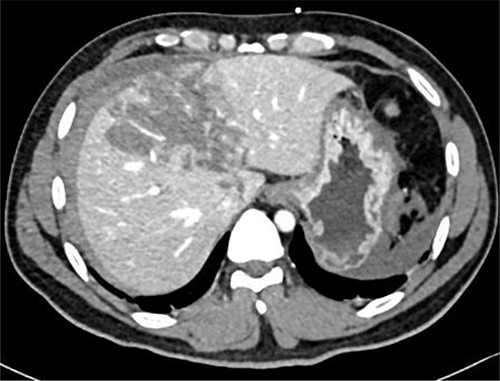

Resuscitation was carried on with 2 l of normal saline and two PRBC units to stabilize the patient. The computed tomography (CT) scan identified Grade 4 liver injury with hemoperitoneum (Fig. 2). Subsequently, the multiple bone fractures underwent surgical fixation, and post-operatively, he was hemodynamically stable. On the fifth day after admission, repeated CT scan demonstrated the liver injury with no evidence of hepatic pseudoaneurysm (Fig. 3). The patient remained stable with tolerated feeding with no abdominal pain or distension. On the Day 17, he developed abdominal pain mainly in the epigastrium, which was associated with nausea and deep epigastric tenderness. Abdominal ultrasound (US) (Fig. 4) and CT scan (Fig. 5) revealed complex, large intraparenchymal hepatic pseudoaneurysm (measuring about 58 × 41 × 30 mm) related to the left hepatic artery Segment 4 branch with surrounding hematoma located mainly at segment 4B/A ,and there was another tiny pseudoaneurysm seen at Segment 4A. Selective angiography confirmed the diagnosis of pseudoaneurysm with multiple blood supplies from Segment IV and Segment II.

Contrast-enhanced CT scan revealing a right hepatic artery pseudoaneurysm in the right lobe of the liver.